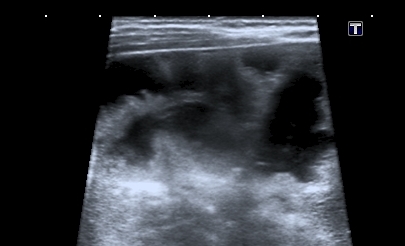

Хочу продолжить дискуссию, повод для этого - сегодняшний пациент 1 года 4 месяцев с клиникой кишечной инфекции и подозрением на инвагинацию. Инвагината не нашёл, но зато при УЗИ выявлены следующие изменения в печени

Кроме того был выражен феномен спонтанного контрастирования кровотока в портальной системе (пузырьки газа?). На рентгенограмме - единичные горизонтальные уровни в тонкой кишке, интерстициального пневматоза стенки газа в проекции портальной системы нет.

В продолжение темы - сходный случай. Ребёнок 5 мес, поступил с признаками энтеральной недостаточности и вздутым животом.

На УЗИ - множественные гиперэхогенные включения в печени. Через 2 дня живот опал, на УЗИ - нормальная печень. Признаков некроза кишечника не было.

Рискну высказать предположение о возможности проникновения газа в портальную систему через неповреждённую, но восппалённую стенку кишки на фоне избыточного давления в её просвете .